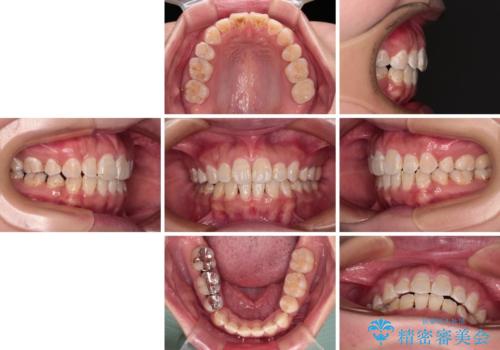

むし歯のリスクが高かったため、治療が長期化しないように心がけました。

当初の予定通り、2年強で無事に治療を終えることができました。